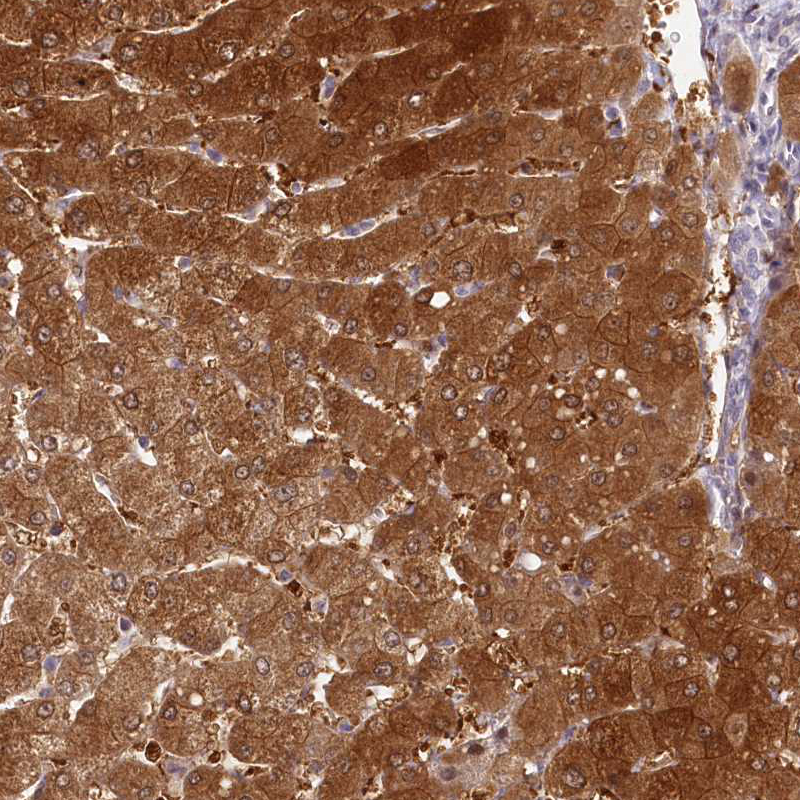

Immunohistochemistry analysis in human liver and endometrium tissues using HPA038322 antibody. Corresponding HPD RNA-seq data are presented for the same tissues.